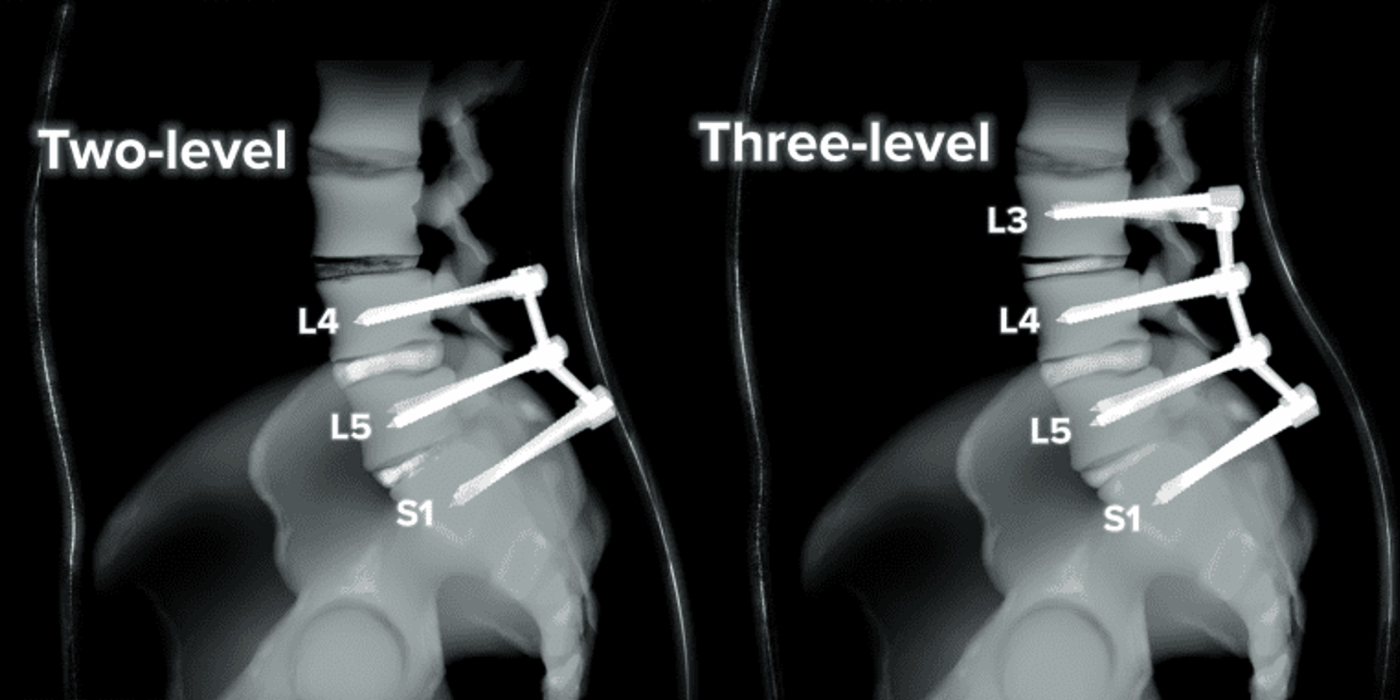

인공 뼈 삽입으로 디스크 높이를 복원한 후 나사못으로 고정하는 수술

• 환자 맞춤 척추 분석

• 각도 / 깊이 / 방향

전부

정확히 맞춤

• 골밀도/골형과

일치하는 대체구조물

• 모든 방향 수술 가능한

고숙련 의료진

• 고령자도 시술 가능한

정밀 수술